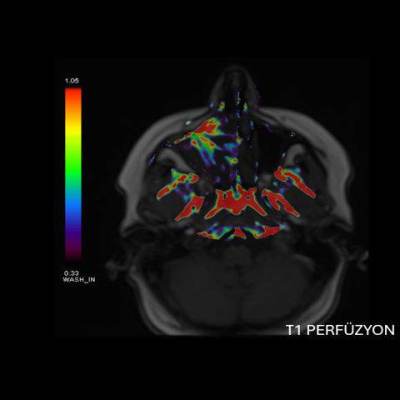

- A) Koronal T2 ağırlıklı görüntülerde sol maksiller sinüs lümenini dolduran, belirgin ‘convoluted’ (karmaşık-kıvrımlı) serebriform patern sergileyen lezyon (oklar), kontrastlı seride heterojen ve yoğun kontrastlanma göstermektedir (oklar). Perfüzyon incelemesinde pedinkülünde perfüzyon artışı gösterdiği, diğer kontrastlanan segmentlerin nispeten hipoperfüze olduğu görülmektedir (ok).

- MR incelemesinde sinonazal inverted papilloma tipik olarak T2 ve post-kontrast T1 serilerde ‘convoluted’ serebriform paternde heterojen sinyal ve kontrastlanma gösteren, pedinküler orijininde daha belirgin perfüzyon artışı sergileyen, genellikle difüzyon kısıtlaması izlenmeyen ve komşu sinüs duvarlarında ekspansiyona bağlı remodelinge yol açabilen benign ancak lokal agresif karakterde bir yumuşak doku kitlesi olarak izlenir.